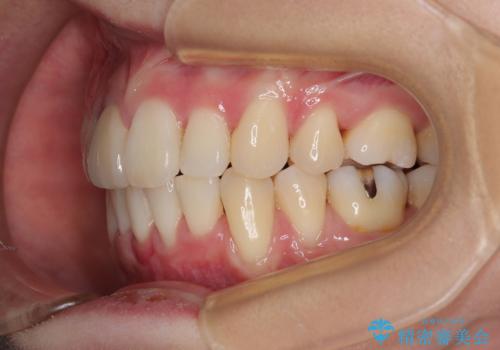

- 八重歯と上の前歯が出っ歯になっていることを気にして来院された患者様です。

横から見た際の口元の飛び出した印象も改善したいとのことで、上下左右の第一小臼歯4本を抜歯し、ワイヤー装置にて抜歯矯正を行うこととしました。

前歯の変色している歯は、神経組織が壊死していたため、矯正治療前に根管治療を実施し、矯正治療後にオールセラミッククラウンにて補綴治療を行うこととしました。

順調に歯が動き、補綴治療も含め2年弱で治療を終えることができました。